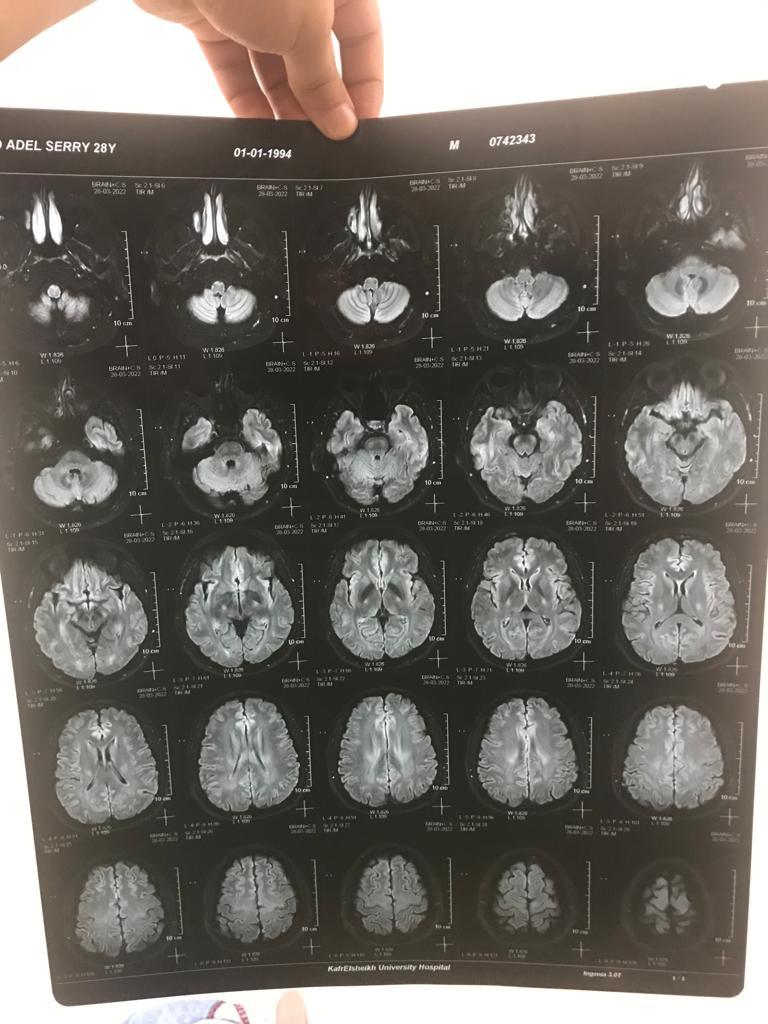

بعد استشارة عدة أطباء، اكتشف أمجد أن السبب هو إصابته بالتصلب الضموري الجانبي، والذي نتج عنه ضمور بالأطراف الأربعة، حيث يتزايد بصورة سريعة منذرا بشلل رباعي.

يروي الدكتور أمجد، ابن محافظة كفر الشيخ لـ القاهرة 24 تفاصيل مرضه: تعبت من شهر يناير اللي فات، ولما كشفت طلع عندي التصلب الضموري، وأخذت العلاج اللي في مصر، مجبش نتيجة.

يقول الطبيب: العلاج بيوقف تطور المرض مش بيعالجه بشكل كامل، وسعر القرص الواحد لمدة 3 أشهر يتراوح بين 30 إلى 35 ألف جنيه، ونفسي صوتي يوصل للمسئولين.